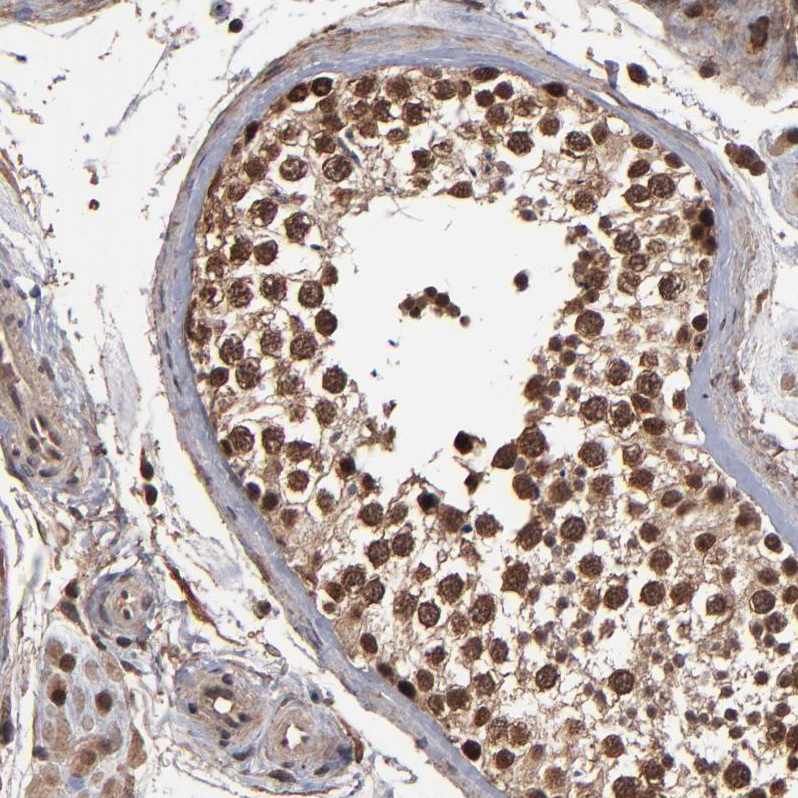

Immunohistochemical staining of human testis shows strong nuclear positivity in cells in seminiferous ducts.